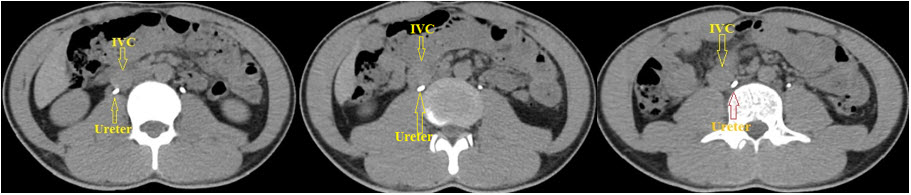

Do nghi ngờ một trường hợp niệu quản bị chén ép bởi tĩnh mạch chủ dưới (IVC), bệnh nhân được chỉ định chụp MSCT Scan để chẩn đoán chính xác và loại trừ các nguyên nhân khác gây ứ nước thận và giãn niệu quản đoạn trên (do sỏi, chèn ép bên ngoài…). Trên các hình ảnh lát cắt ngang, thấy thận phải giãn nhẹ, niệu quản giãn đến đốt sống L3 thì quặt vào trong chạy sau IVC (Hình 3).

tietnieu3

Hình 3. MSCT Scan cho thấy niệu quản phải chạy vào trong sau IVC